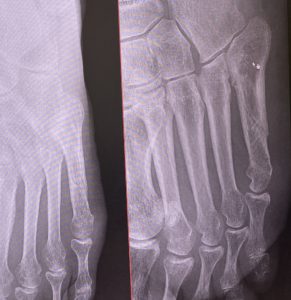

3ヶ月経った状態のレントゲン写真です。

骨はくっついている感じですが、斜めからのショットを見る限りは今後の衝撃度によってはバキッとなりそうです。